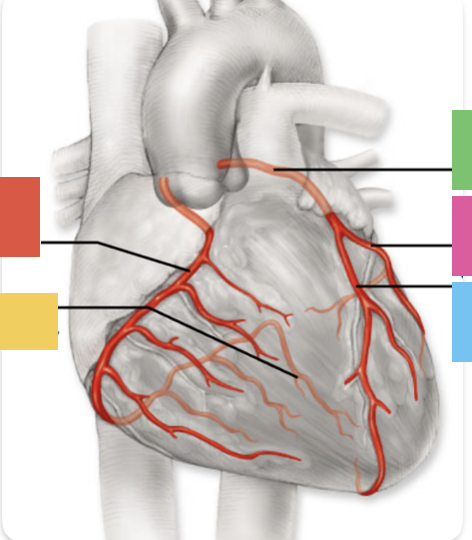

red

right coronary artery

yellow

posterior interventricular artery

green

left coronary artery

blue

anterior interventricular artery

pink

circumflex artery

coronary sinus